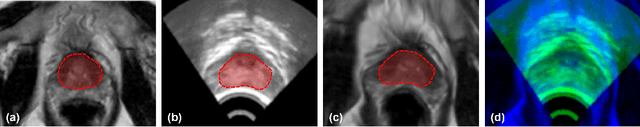

Abstract:Purpose: Accurate 3D MRI-ultrasound (US) deformable registration is critical for real-time guidance in high-dose-rate (HDR) prostate brachytherapy. We present a weakly supervised spatial implicit neural representation (SINR) method to address modality differences and pelvic anatomy challenges. Methods: The framework uses sparse surface supervision from MRI/US segmentations instead of dense intensity matching. SINR models deformations as continuous spatial functions, with patient-specific surface priors guiding a stationary velocity field for biologically plausible deformations. Validation included 20 public Prostate-MRI-US-Biopsy cases and 10 institutional HDR cases, evaluated via Dice similarity coefficient (DSC), mean surface distance (MSD), and 95% Hausdorff distance (HD95). Results: The proposed method achieved robust registration. For the public dataset, prostate DSC was $0.93 \pm 0.05$, MSD $0.87 \pm 0.10$ mm, and HD95 $1.58 \pm 0.37$ mm. For the institutional dataset, prostate CTV achieved DSC $0.88 \pm 0.09$, MSD $1.21 \pm 0.38$ mm, and HD95 $2.09 \pm 1.48$ mm. Bladder and rectum performance was lower due to ultrasound's limited field of view. Visual assessments confirmed accurate alignment with minimal discrepancies. Conclusion: This study introduces a novel weakly supervised SINR-based approach for 3D MRI-US deformable registration. By leveraging sparse surface supervision and spatial priors, it achieves accurate, robust, and computationally efficient registration, enhancing real-time image guidance in HDR prostate brachytherapy and improving treatment precision.